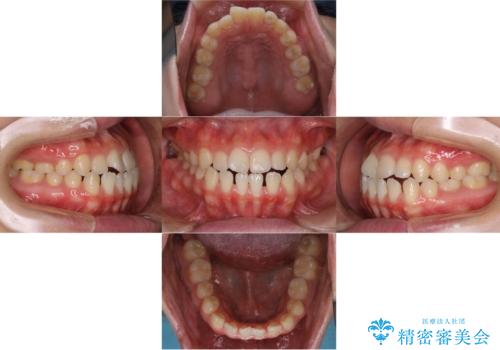

- やや受け口なのと、下の歯の隙間が気になるとのことで来院された患者様です。

下の前歯の歯茎がとても薄く、このままでは歯茎が下がってしまうリスクがありました。

また、オープンバイト(開咬)もありました。